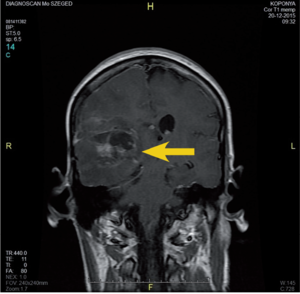

3.6.2. Daganatok: az agy (64–72. ábra)

- MRI: T2, FLAIR, T1/T1gad, DWI.

- CT: natív és kontrasztos – akut eset, staging, mész kimutatására.